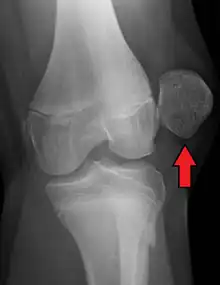

X-ray showing a patellar dislocation, with the patella out to the side.

A patellar dislocation is a knee injury in which the patella (kneecap) slips out of its normal position.[5] Often the knee is partly bent, painful and swollen.[1][2] The patella is also often felt and seen out of place.[1] Complications may include a patella fracture or arthritis.[3]